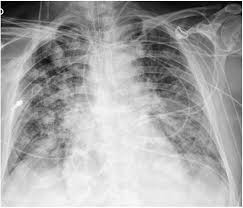

Pediatric Chest X-ray Pneumonia Detection

A deep learning model to detect pneumonia from pediatric chest X-rays.